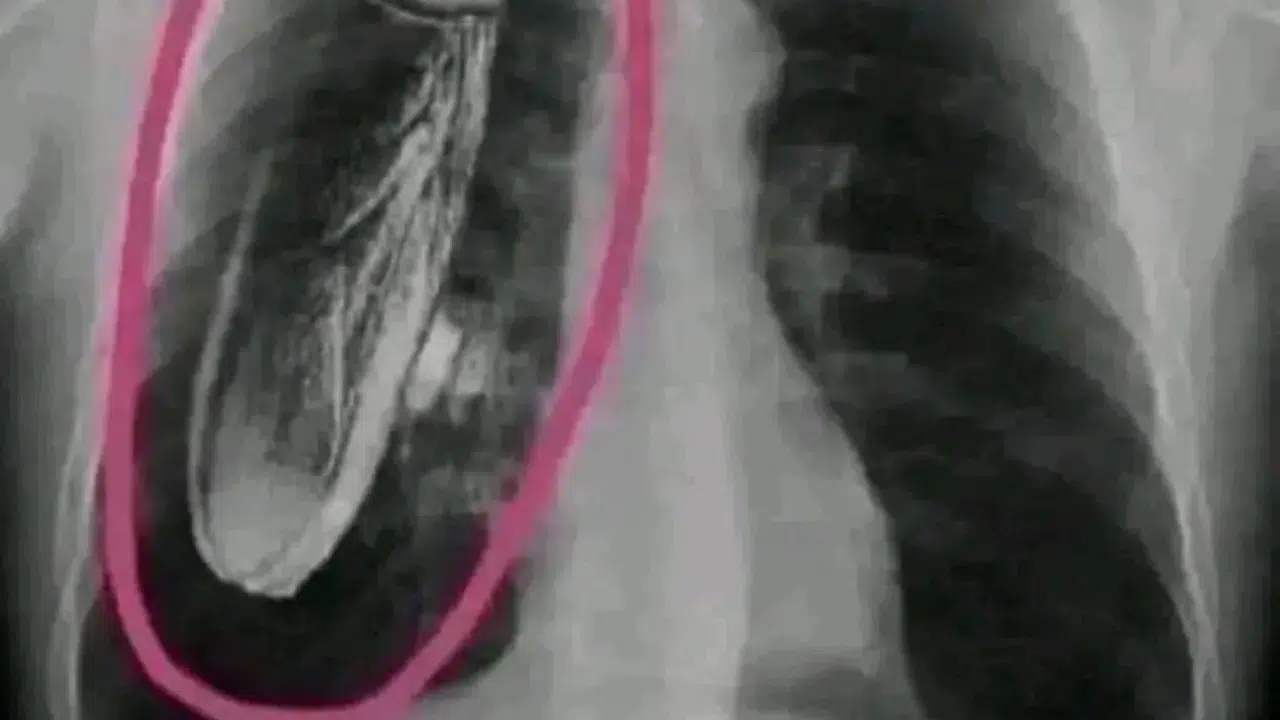

Kenya'daki bir devlet hastanesinde bir hastanın röntgeni çekildi ve göğsünde canlı bir hamamböceği olduğu söylendi. "Tedavi için Singapur'a gitmeniz gerekecek."

Hasta Singapur'a gitti ve hamamböceğinin göğsünde değil, röntgen makinesinin içinde olduğu söylendi.